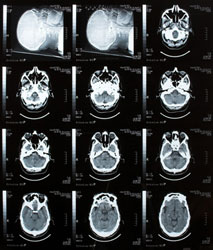

An interruption to the blood supply to the brain even partially may cause a rapidly developing loss of brain function. Stroke is treated as a medical emergency and may lead to a permanent neurological damage or even death unless it is early diagnosed and treated. Due to its size and complexity, stroke incidents have increased over the past years. Nowadays, it is considered to be the third leading cause of death and the main cause of disabilities in the Western world. Urged by this the UMEDS project aimed at reducing the impact of stroke through early diagnosis, prompt therapy and reliable monitoring. With the aid of new non-invasive technologies the project focused on improving the quality of life of patients affected by stroke. By exploiting latest developments in micro-bubble technology and ultrasonographic harmonic imaging new ultrasound techniques and technologies were realised. As such, an ultrasonic device for brain scanning was also produced. On the basis of time reversal mirrors, the new, fully programmable prototype developed allows compensation of distortion due to inhomogeneous media. The innovative ultrasonic scanner uses a novel aberration correction algorithm for high resolution imaging of the brain. The innovative feature of the new ultrasound brain scanner is that it provides a very good correction of the defocusing effect of the skull during the calibration process. At the end of the calibration process that lasts only one minute, the set of emission signals is stored in the electronics offering real time images. The device was used to gather high resolution in vitro images transcranially. The promising results showed that the prototype could completely restore the resolution and enhance the contrast as compared to classical imaging. The capabilities of this breakthrough technology will be further explored also in the case of real time in vivo brain imaging.